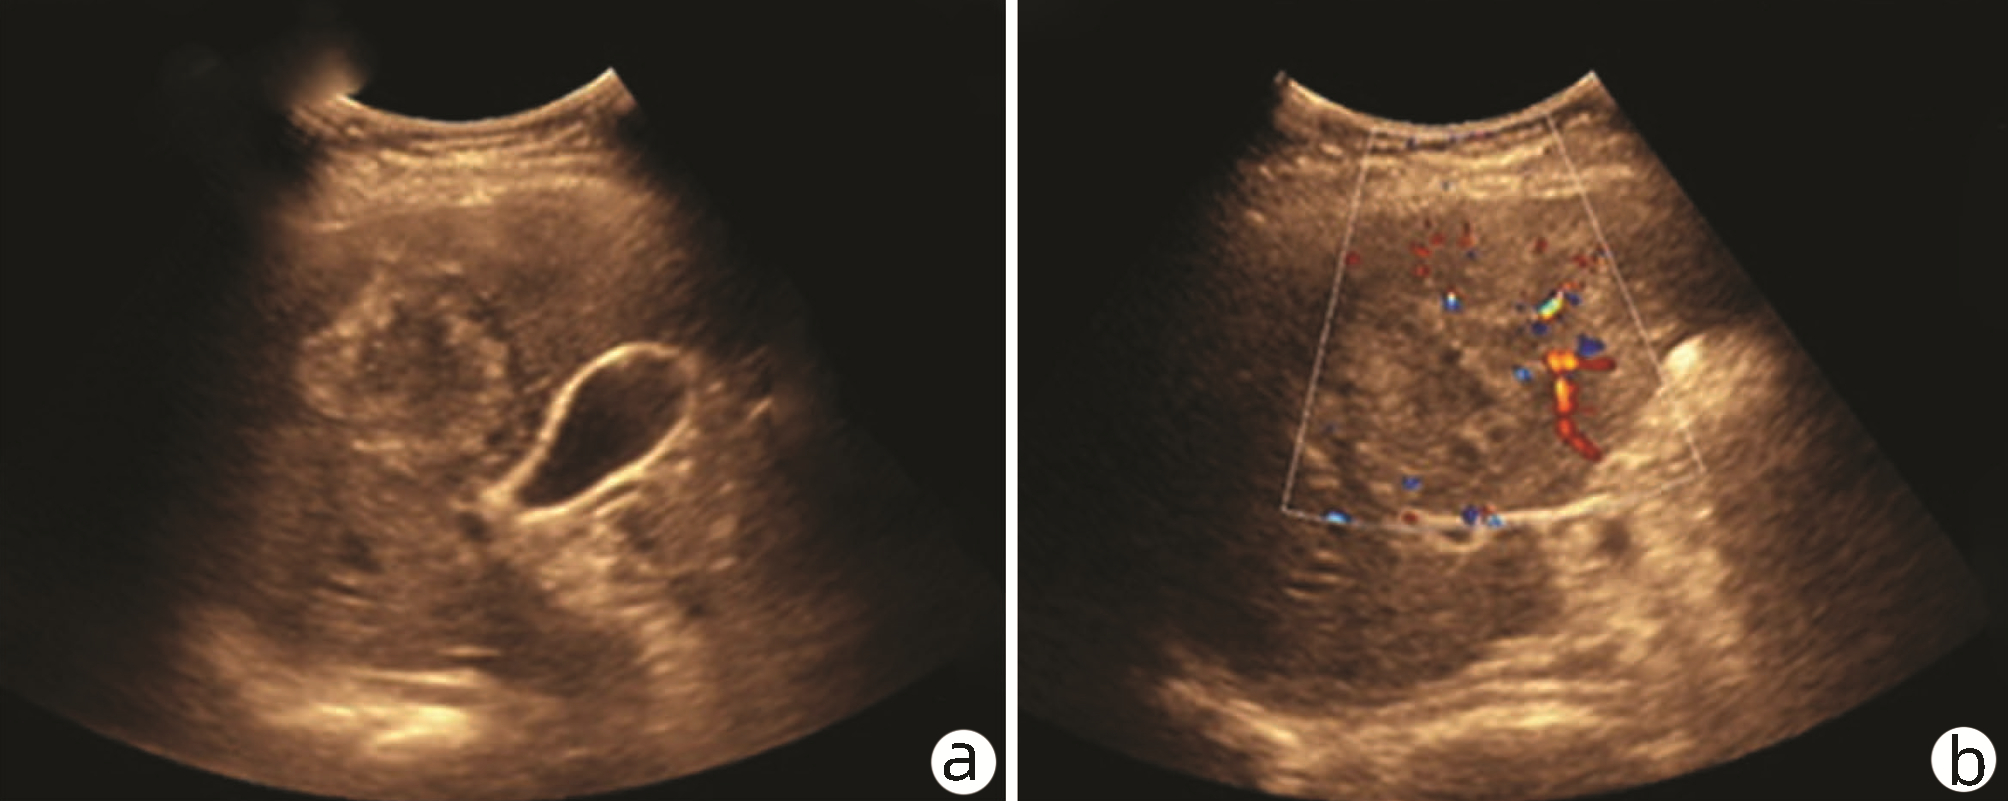

Ultrasound findings and contrast-enhanced ultrasound findings of mass-type autoimmune pancreatitis versus pancreatic ductal adenocarcinoma

Xiangliu OUYANG, Yunxia HAN, Lichun ZHENG, Yingchun ZHAO, Xinyu SHEN, Wenjun ZHANG, Yanbin WANG

2022, 38(6): 1351-1355. DOI: 10.3969/j.issn.1001-5256.2022.06.025

Abstract(1427) HTML (553) PDF (3738KB)(50)

Abstract:

Objective  To investigate the value of ultrasound and contrast-enhanced ultrasound (CEUS) in the differential diagnosis of mass-type autoimmune pancreatitis (AIP) and pancreatic ductal adenocarcinoma (PDAC).  Methods  A retrospective analysis was performed for the clinical data, ultrasound findings, and CEUS findings of 11 patients with mass-type AIP who were diagnosed in Tangshan Workers' Hospital from January 2015 to December 2020, and their characteristic manifestations were analyzed and compared with the data of 23 patients with PDCA. The chi-square test was used for comparison of categorical data between two groups.  Results  For the 11 patients with mass-type AIP, CEUS had a diagnostic accuracy of 63.64%, and all of these patients had hypoechoic single lesions; the patients with clear boundaries, regular morphology, pancreatic duct dilatation or cutoff, and blood flow signal accounted for 54.55%, 63.64%, 18.18%, and 36.36%, respectively, while in the PDCA group, such patients accounted for 30.43%, 34.78%, 78.26%, and 21.74%, respectively, and there was a significant difference in the presence or absence of pancreatic duct dilatation or cutoff between the two groups(χ2=11.089, P < 0.05), with no significant differences in the other indices (all P > 0.05). For the 11 patients with mass-type AIP, CEUS showed that 7 patients (63.64%) had hyperenhancement and 4 (36.36%) had iso-enhancement in the arterial phase, and 5 patients (45.45%) had hyperenhancement in the arterial phase and 6 (54.55%) had iso-enhancement in the venous phase; for the 23 patients with PDCA, 22 (95.65%) had hypoenhancement of lesions in both arterial and venous phases, and there were significant differences in the enhancement pattern in arterial and venous phases between the two groups (χ2=30.345 and 30.084, both P < 0.05).  Conclusion  The enhancement pattern of CEUS and the presence or absence of pancreatic duct dilatation or cutoff have a relatively high value in the differential diagnosis of mass-type AIP and PDCA.